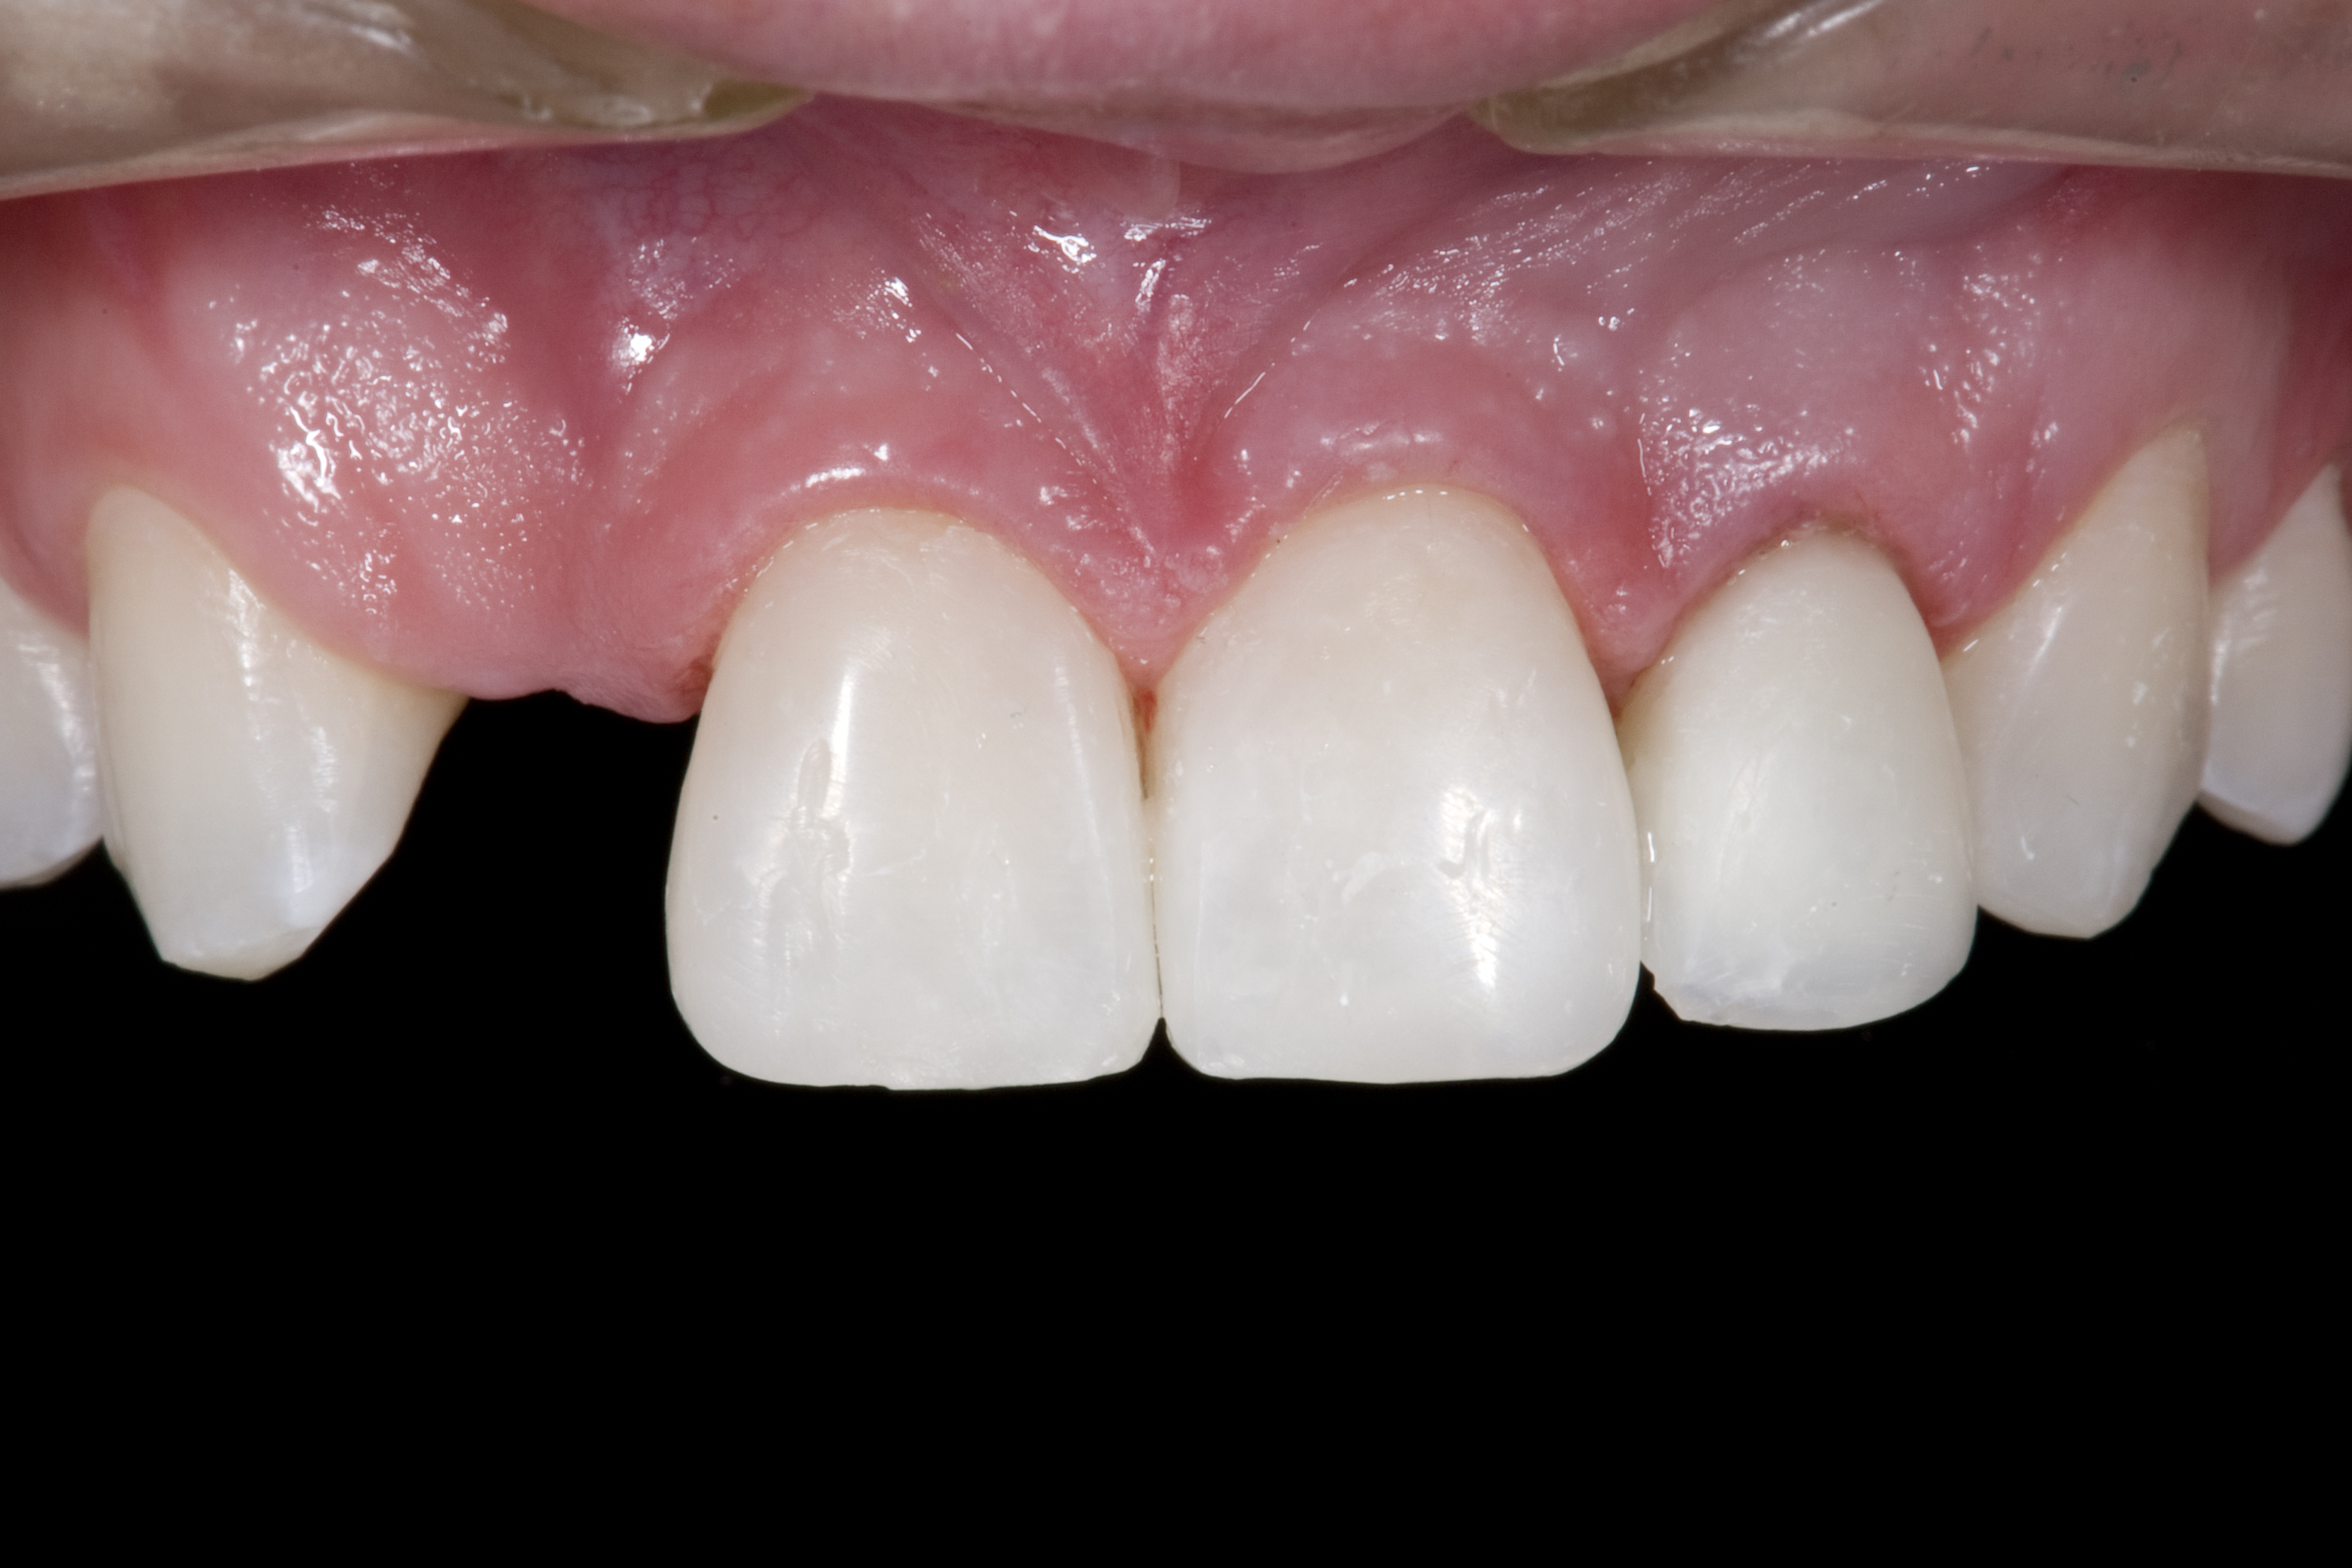

(2.) After orthodontic alignment of teeth and bleaching. Note alveolar deficiency in right lateral incisor site and diminutive left lateral incisor.

Figure 2

A 14-year-old patient presented to the office with his mother (Figure 1). His chief complaint involved the large spaces between the teeth created by his missing right maxillary lateral incisor and his small left maxillary lateral incisor. He desired to replace the missing tooth with an implant and create a beautiful smile. Upon examination, he was found to have a class I canine and molar relationship, but because he had a tooth size/arch size discrepancy and space distal to the right central incisor, the remaining incisors had drifted to the right. The left maxillary lateral incisor was peg-shaped and in a cross bite position. Studies have shown a clear association between congenitally missing teeth and reduced tooth size.59-62 Because he was only 14-years-old at the time and could not have implants placed until the cessation of growth (somewhere in the vicinity of 22 years old), he was sent to the orthodontist for alignment of the teeth.16,17 After 2 years of orthodontics, the appliances were removed, and his tooth coloration was improved using carbamide peroxide bleaching (Figure 2). Because some form of provisional needed to be placed until he was finished growing, a double-wing metal resin-bonded bridge was chosen. As discussed earlier, this is the ideal transitional prosthesis for patients that have congenitally missing maxillary lateral incisors. The benefits of this type of prosthesis include its ability to be removed and rebonded during the surgical phase of treatment and its ability to retain the roots in their proper position after orthodontic treatment.16 The final plan for the patient was to increase the width of the central and the maxillary left lateral incisor, utilizing porcelain laminate veneers to achieve the appropriate width/length ratio of 80%. A wax-up was created to idealize tooth size, a putty matrix was made from the wax-up to facilitate bonding of the incisors, and a non-precious, double-wing metal resin-bonded bridge was fabricated for lateral incisor replacement. Once the teeth were bonded to ideal size, the “Maryland Bridge” was fabricated from a polyvinyl arch impression with the newly bonded teeth (Figure 3). The metal frame was cast from a non-precious alloy to allow for fabrication of a very thin frame and to create a better surface for bonding. After sandblasting the internal aspect of the frame with CoJet™ silica (3M ESPE), accomplishing salinization, and executing cementation with a dual-cure resin cement, a fairly good adhesion to the frame was anticipated.29 The enamel surface was etched with phosphoric acid for 30 seconds, the primer (Single Bond Plus, 3M ESPE) was applied to both the internal surface of the sandblasted framework and the etched enamel, and the bridge was cemented with RelyX™ ARC (3M Espe) dual-cured resin cement (Figure 4 and Figure 5).